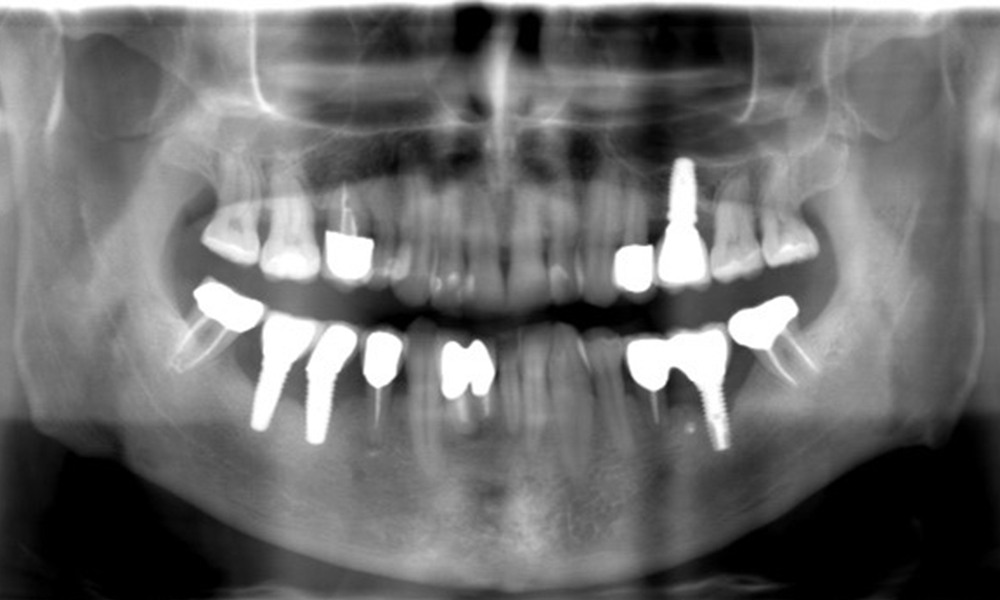

The X-ray images show the progression of bone loss. OPG from 29.06.2020 (left) and OPG from 26.02.2024 (right).

OPG: 26/02/2024 Dental X-ray: 18/01/2024